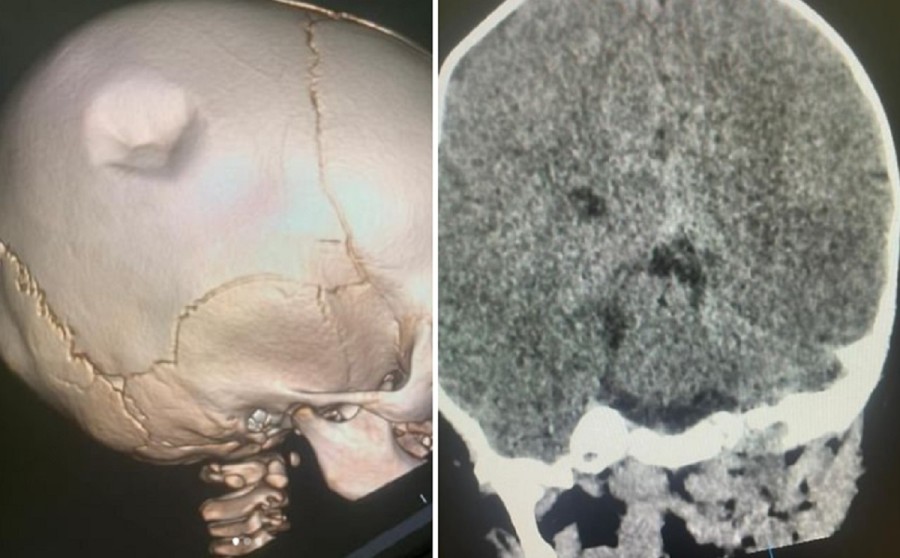

Результаты КТ пострадавшего ребёнка. Фото Ербола Кенжевалова

- Ребёнок поступил с жалобами на беспокойность и вмятину в области головы. Малыш был в сознании, отказывался брать грудь. При поступлении в больницу у него был диагностирован вдавленный перелом теменной кости, ушиб головного мозга. По словам родителей, четырёхлетний брат малыша по неосторожности пнул его по голове. Нам удалось приподнять вдавленный перелом, - рассказал детский нейрохирург Ербол Кенжевалов.